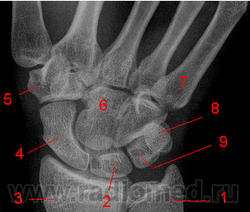

Кости запястья.

Рис. 2. 1. Шиловидный отросток локтевой кости.  2. Полулунная кость. 3. Лучевая кость. 4. Ладьевидная кость. 5. Кость-трапеция. 6. Трапециевидная кость. 7. Головчатая кость. 8. 5 пястная кость. 9.  Крючковидная кость.